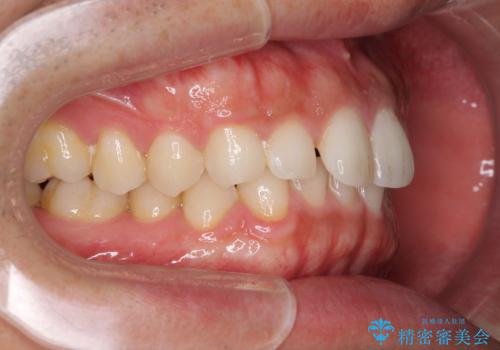

細かい隙間にものがはさまる インビザラインによる矯正治療

- 上下の前歯の隙間を気にして来院された患者様です。

インビザラインを用い、上下歯列のスペースを閉じていくこととしました。

銀行にお勤めのため、突然の転勤により通院が大変な状況となりましたが、インビザラインであれば2-3ヶ月に1度を目安に来院いただき、無事に治療を終えることができました。